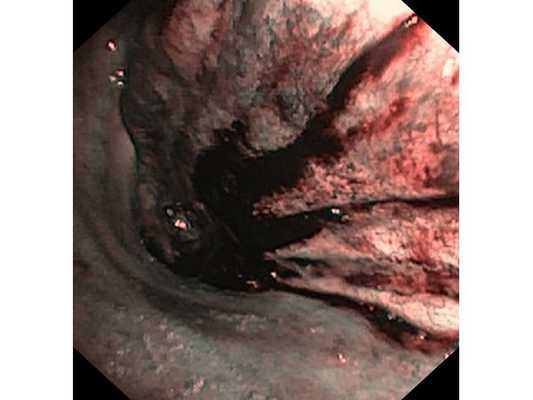

Первым этапом пациенту была проведена фибробронхоскопия, по данным которой выявлено, что устье нижнедолевого бронха слева сужено за счёт подслизистого и перибронхиального распространения опухоли.

Выполнена многократная биопсия из устья нижнедолевого бронха слева. По данным гистологического исследования материала эндоскопической биопсии верифицирован диагноз немелкоклеточного рака лёгкого.